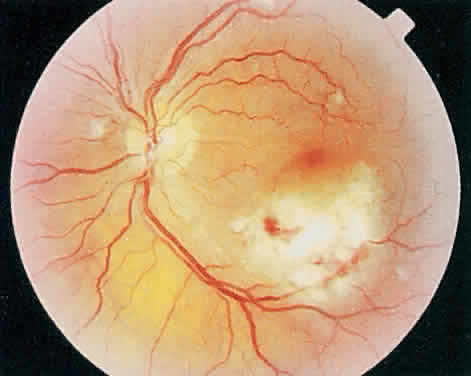

Over a course that usually spans weeks, infiltrates of CMV tend to assume two different patterns of clinical disease.11,12 The first pattern is called hemorrhagic and is characterized by broad geographic zones of retinal whitening. These large, geographic lesions are usually in close proximity to a major retinal blood vessel or the optic nerve. Satellite lesions are common. When the retinal necrosis associated with CMV retinitis becomes widespread, it is almost invariably associated with retinal hemorrhages. Although the border between necrotic and unaffected retina is sharply demarcated, the border itself appears irregular and jagged. Exudation into the retina or subretinal space may be seen, adding to the granular appearance of the retinitis. Juxtaposition of large zones of white, granular necrosis with those of red retinal hemorrhage has led this appearance of CMV retinitis to be described as either “pizza-pie” or “cheese and ketchup.” The retinal blood vessels, both arteries and veins, in the areas of necrosis commonly appear sheathed, secondary to a vasculitis. As a consequence, secondary retinal vascular occlusions, especially branch retinal vein obstructions, may occur in the course of CMV retinitis. Immune-mediated vascular damage may play a role in the vasculitis.12 Central healing of these lesions will occur as the infection progresses. Avasculitis resembling “frosted branch angiitis” hasbeen reported (Fig. 2).28 A second pattern of CMVretinitis has been labeled “granular” or “brushfireborder.” In this appearance, the focal granular infiltrates enlarge slowly across a line, leaving ever-increasing areas of destroyed retina and atrophic retinal pigment epithelium behind. Hemorrhages and vitreous cells are a less prominent feature. There appears to be direct cell-to-cell transfer of infected virions in this pattern of infection (Figs. 3 and 4). The brushfire border is commonly seen in CMV retinitis lesions anterior to the equator (Fig. 5). The significance, if any, of these two clinical patterns of CMV retinitis is not known, and, in some eyes, both patterns of disease can be seen simultaneously or in sequence. Progression of retinitis has been defined in clinical trials as movement of a lesion border at least 750 μm along a front that is 750 μm or more in length, development of a new CMV lesion in a previously involved eye or in the uninvolved fellow eye of a patient with baseline unilateral disease.29 Without treatment or improvement in the host's immune system, CMV retinitis is a relentless, slowly progressive infection resulting in blindness caused by total retinal necrosis, retinal detachment, or optic nerve involvement, in any combination.

Fig. 3. Active cytomegalovirus retinitis adjacent to the optic nerve. Visual acuity was counting fingers.

Fig. 4. Three months later the retinitis has completely destroyed the retina leaving a visual acuity of no light perception.